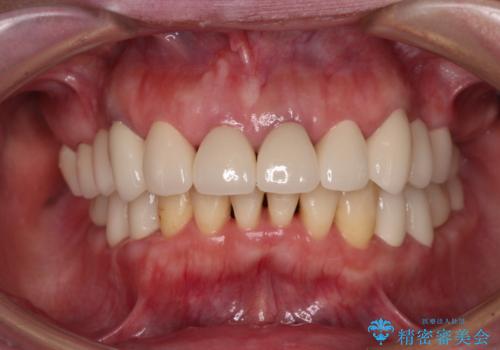

インプラントに対する恐怖心が強く、欠損補綴は極力ブリッジを採用し、インプラントの数は必要最小限としました。

油断をするとすぐに汚れが溜まって歯肉が腫れてきてしまうため、今後も定期的なメインテナンスが重要となります。